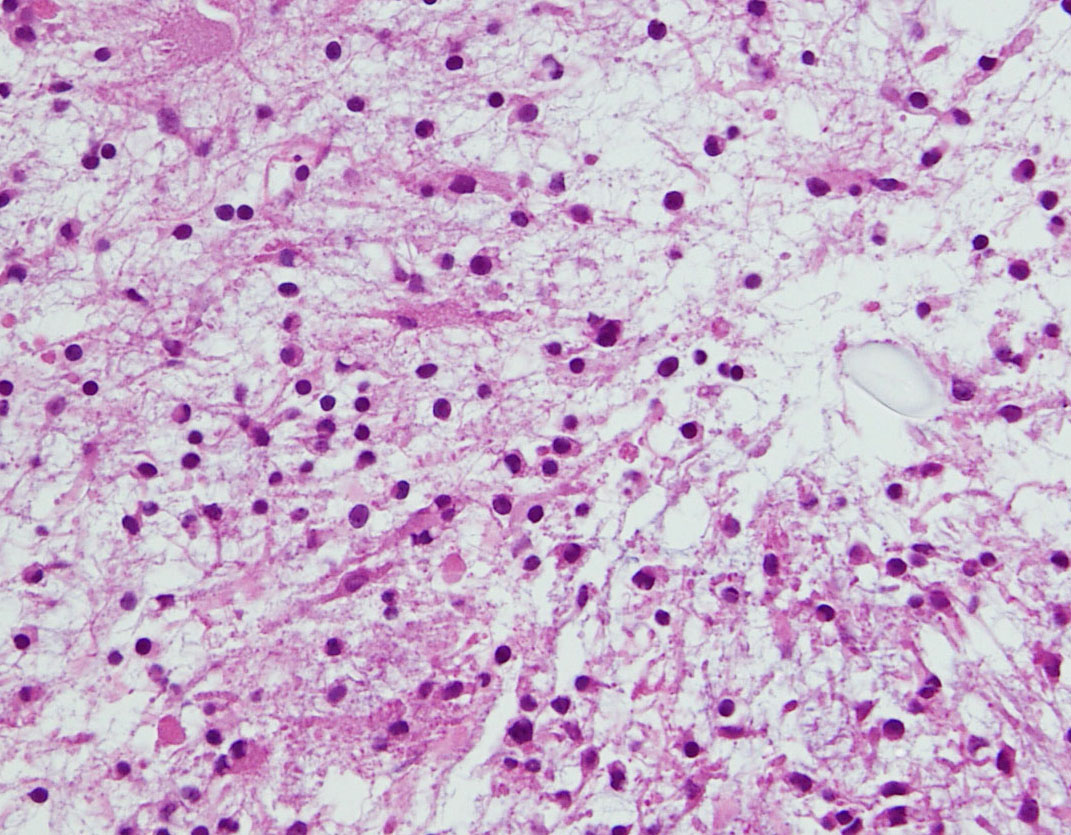

幼児の毛様細胞性星細胞腫

血管に富み,増大傾向が著しかった例です。MIB-1(右下)が20%以上あり異常に高値でした。